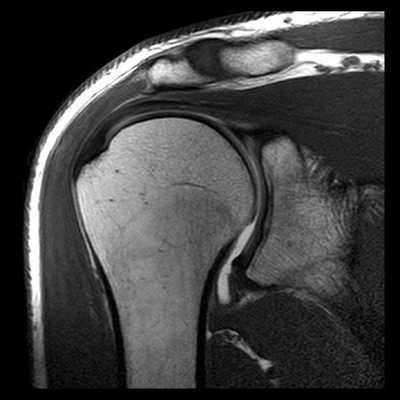

МРТ плечевого сустава. Т2-взвешенная корональная МРТ. Разрыв вращательной манжеты. Цветовая обработка изображения.

МРТ плечевого сустава. Корональные Т1-взвешенные МРТ. Переломы Хилла-Сакса и Банкарта.

МРТ. Корональная Т2-зависимая томограмма с подавлением сигнала от жира. Полный разрыв сухожилия надостной мышцы.

МРТ плечевого сустава с подавлением сигнала от жира. Т2-взвешенная корональная МРТ. Перелом большого бугорка (стрелка).

При МРТ плечевого сустава косвенным признаком разрыва вращательной манжеты служит высокий сигнал на Т2-взвешенных от поверхности сустава до субакромиальной (субдельтовидной) сумки. Частичные разрывы чаще всего по передней поверхности сухожилия м.supraspinatus, реже примыкая к большой бугристости или сухожилия м. infraspinatus.

МРТ плечевого сустава. Т2-взвешенная корональная МРТ. Субакромиальное скопление жидкости - косвенный признак разрыва вращательной манжеты.

МРТ плечевого сустава. Т1-взвешенная корональная МРТ. Частичный разрыв вращательной манжеты.

МРТ плечевого сустава. Т2-взвешенная корональная МРТ. Передний разрыв вращательной манжеты